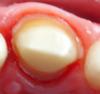

Cons Опубликовано 12 декабря, 2012 Поделиться Опубликовано 12 декабря, 2012 Вот сделали обточку. Подскажите на сколько соблюдены все правила качественно ли она сделана? Ссылка на комментарий

Cons Опубликовано 12 декабря, 2012 Автор Поделиться Опубликовано 12 декабря, 2012 (изменено) Она есть, просто попросил сделать фото перед установкой времянки. А что за огрехи? Как отразится на эксплуатации? Вот еще есть фото с низу: Изменено 12 декабря, 2012 пользователем Cons Ссылка на комментарий

Prosthodontist Опубликовано 12 декабря, 2012 Поделиться Опубликовано 12 декабря, 2012 слишком глубокое препарирование под десну, а так видно что старались 1 Ссылка на комментарий